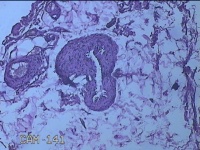

外阴部包块

性别

女

年龄

37岁

临床诊断

皮脂腺囊肿

一般病史

外阴部起包块一月余。

标本名称

大体所见

灰白暗红色包块2.3x1.8x0.8cm一个,表面糜烂,切开包块呈实性,切面灰白淡黄色,质软。

有那么点像脂肪瘤。